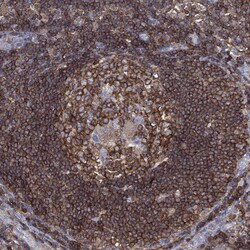

Invitrogen™ DOCK8 Polyclonal Antibody

Brand: Invitrogen™ PA5140262

Gently mix before use. Optimal concentrations and conditions for each application should be determined by the user. Immunogen sequence: INRYSSAEIR KQFTLPPNLG QYHRQSISTS GFPSLQLPQF YDPVEPVDFE GLLMTHLNSL DVQLAQELGD FTDDDLDVVF Highest antigen sequence indentity to the following orthologs: Mouse - 88%, Rat - 86%.

The Dedicator of cytokinesis protein 8 (DOCK8) is a member of the DOCK180 family of guanine nucleotide exchange factors. DOCK8 plays an essential role in humoral immune responses and is important in the proper formation of the B cell immunological synapse. Mutations in this gene result in the autosomal recessive form of the hyper-IgE syndrome.

| Immunohistochemistry (Paraffin), Western Blot | |

| Recombinant protein corresponding to Human DOCK8. Recombinant protein control fragment (Product #RP-109342). | |